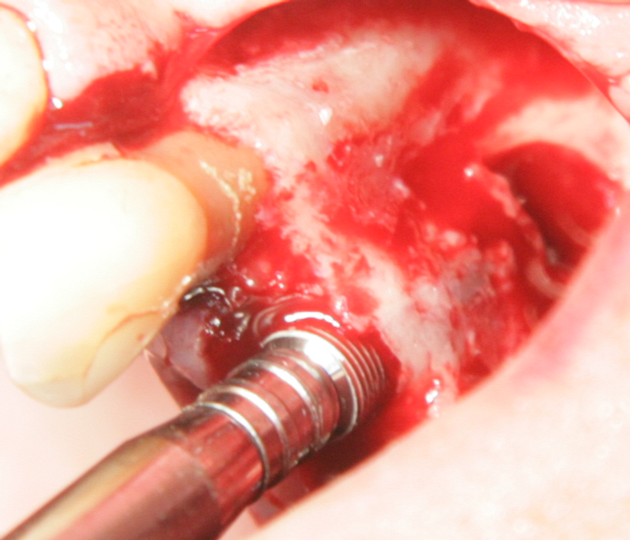

Отворен максиларен синус в началото на интервенцията. Случаят е интересен със следното - твърде атипична форма на трепанационния отвор. На какво се дължи на това - на лошо планиране на оперативния достъп или на нещо друго? Дължи се на факта, че отначало въпросната намеса беше планирана като балонен синуслифт; за съжаление обаче мембраната на синуса се разкъса и надуването на балона стана невъзможно.